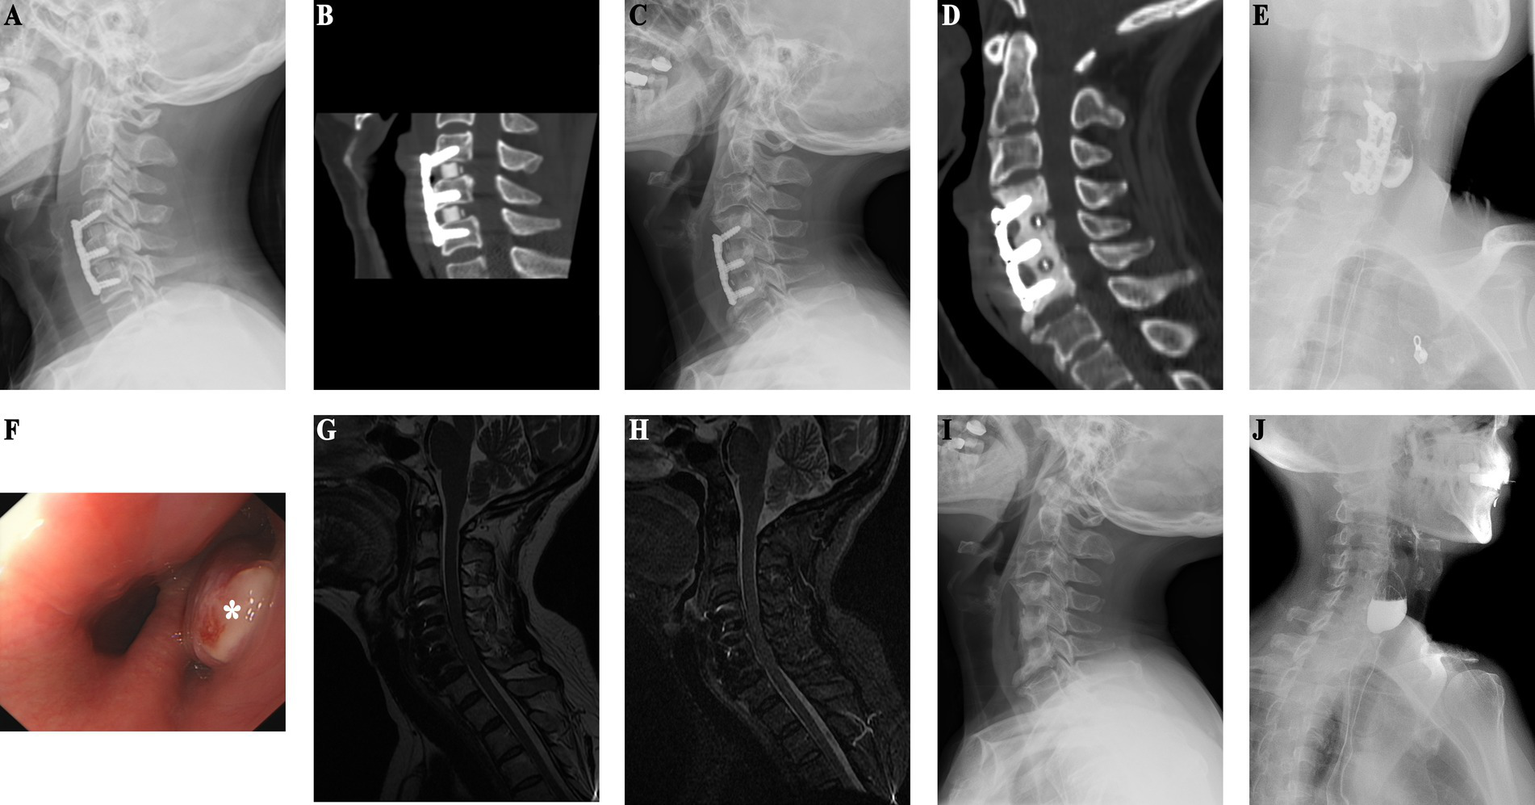

Case 1

An adult patient with myelopathy underwent C6 ACCF in 2004. She developed right neck and shoulder pain and was suspected to have an esophageal perforation based on esophagography performed 6 months postoperatively. However, gastrointestinal endoscopy did not confirm the presence of an esophageal perforation. Over the next 7 years, she experienced persistent pain and sought medical attention multiple times without receiving a diagnosis. At 7 years postoperatively, she developed a mass in the right neck that was unable to be located during biopsy attempts. At 10 years postoperatively, she was diagnosed with lymphoma, which was later revealed to be caused by an esophageal perforation. On cervical radiography, the internal fixation of the cervical spine was structurally good, but there was a local bone defect in the C5–7 vertebrae under the steel plate (Figure 1A). CT showed a partial bone defect in the C5–7 vertebral bodies and swelling of the right paravertebral soft tissue with pneumata and effusion (Figure 1B). MRI showed localized swelling and effusion in the paravertebral soft tissues (Figures 1C,D). During esophagography, the contrast agent leaked into the soft tissues of the cervical spine to reveal a large surrounding cavity (Figure 1E). Gastrointestinal endoscopy revealed an esophageal diverticulum, a 5-cm-long ulcerative defect in the posterior wall of the esophagus, and a visible cervical steel plate (Figure 1F). Surgery revealed a large esophageal diverticulum with rupture, which was treated with esophagoplasty and muscle flap closure. Two years after the final esophageal perforation repair, X-ray shows preserved cervical spine curvature, C5-7 vertebral body bone loss, and removal of internal fixation (Figure 1G). MRI T2-weighted and STIR images demonstrate mixed anterior high and low signal intensity with partial vertebral body defects (Figures 1H,I). Esophagography shows a 2.0 x 0.6 cm intraluminal esophageal outpouching (Figure 1J). After 8 years of follow-up, her symptoms had resolved and the wound had healed.

Figure 1

(Case 1) (A) Ten years post-cervical spine surgery, X-ray reveals bone resorption in the C5–7 vertebral bodies beneath the plate, with anterior plate pneumatisation. (B) CT shows partial osseous defect in the C5–7 vertebral bodies, accompanied by anterior soft tissue swelling and pneumatosis. (C) T2-weighted sequence shows anterior soft tissue pneumatosis and fluid accumulation. (D) STIR sequence depicts partial vertebral body loss and anterior high signal intensity. (E) Esophagography demonstrates extraluminal contrast extravasation into the cervical spine soft tissues, with a surrounding cavity measuring approximately 2.9 × 1.0 cm. (F) Upper endoscopy reveals esophageal diverticulum and a 5 cm posterior esophageal wall rupture defect, with visualization of the cervical spine plate. (G) Two years post-esophageal perforation repair, X-ray demonstrates preserved cervical spine physiological curvature, removal of cervical spine internal fixation, and localized C5–7 vertebral body bone loss. (H) Two-year postoperative cervical spine MRI T2-weighted images exhibit mixed anterior high and low signal intensity. (I) Postoperative STIR images illustrate partial vertebral body defects and anterior high signal intensity. (J) Postoperative esophagography reveals 2.0 × 0.6 cm intraluminal esophageal outpouching.

Case 2

Patient in their 40s who underwent C4–6 ACDF surgery 9 years ago for cervical spondylosis was admitted for intestinal tumor evaluation (Figures 2A,B). Due to her surgical history, she underwent cervical spine imaging that revealed thickened prevertebral soft tissue, bone resorption under the steel plate, and marginal osteosclerosis (Figure 2C). CT confirmed the presence of bone resorption and soft tissue thickening. There was also increased bone density at C4–6 (Figure 2D). An esophageal perforation was suspected. MRI showed soft tissue swelling in front of the vertebral C4–6 (Figures 2G,H). Gastrointestinal endoscopy revealed esophageal bulging (Figure 2F), and esophagography confirmed diverticulum formation (Figure 2E). The patient underwent surgical removal of the diverticulum and internal fixation, with esophagoplasty and muscle flap closure. Half a month after esophageal perforation repair, X-ray shows removal of C4-6 internal fixation with a localized vertebral defect (Figure 2I), and esophagography reveals a 2.8 x 1.9 cm residual contrast pouch in the upper esophagus (Figure 2J). She recovered well and had no discomfort during 4 years of follow-up, suggesting that she had experienced an occult esophageal perforation.

Figure 2

(Case 2) (A) One-year postoperative follow-up X-ray after ACDF shows preserved physiological curvature of the cervical spine with no signs of loosening of internal fixation. (B) One-year post-ACDF CT reveals no evidence of bone resorption beneath the plate. (C) X-ray findings nine years post-ACDF demonstrate significant bone absorption and increased density in the vertebral bodies at the C4–6 level. (D) CT findings are consistent with X-ray results. (E) Esophagography indicates residual contrast material in a localized pouch-like formation in the upper segment of the esophagus, measuring approximately 3.3 × 2.7 cm. (F) Endoscopic examination reveals a bulge in the esophagus approximately 15 cm distal to the incisors (as indicated by * in the diagram). (G) T2-weighted sequence shows high mixed signal intensity anterior to the vertebral bodies at the C4–6 level. (H) STIR sequence demonstrates pronounced anterior soft tissue swelling. (I) Half-month post-esophageal perforation repair X-ray shows removal of internal fixation devices at the C4–6 level, with localized vertebral body defect. (J) Postoperative esophagography reveals residual contrast material in a localized pouch-like formation in the upper segment of the esophagus, measuring approximately 2.8 × 1.9 cm.